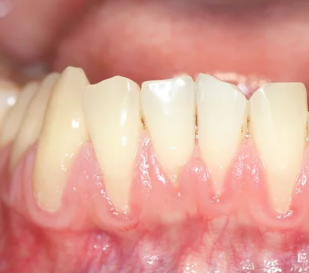

4. 잇몸이 내려가고 치아가 길어 보인다 – 잇몸 퇴축 현상

잇몸뼈가 녹아내리면, 잇몸이 치아뿌리 쪽으로 물러나면서 치아가 길어 보이는 현상이 나타납니다.

- 거울로 보면 치아가 평소보다 길게 보임

- 잇몸 경계가 울퉁불퉁하고 균일하지 않음

- 찬물 마실 때 시림이 심해짐

▶ 치아가 길어지는 건 단순한 미용 문제가 아닌 치아지지 구조 약화의 증거입니다.